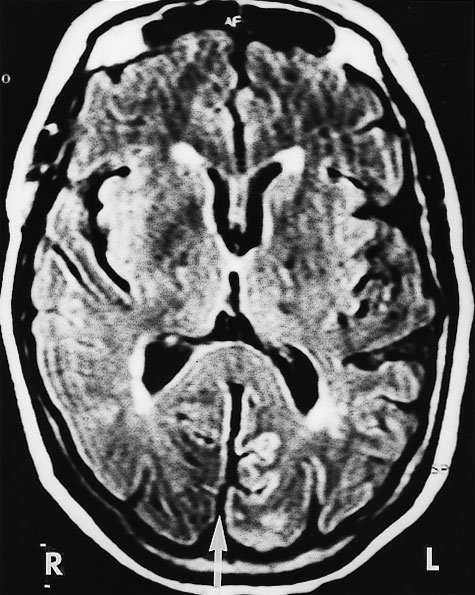

Computed tomography (CT) brain scan was performed three hours after the completion of coronary angiography. No additional contrast was used. The CT brain scan (Box 1) showed marked bilateral contrast enhancement of the occipital lobes and no evidence of a cerebral haemorrhage. Intravenous heparin treatment was commenced. By the following day, she was able to see shapes and shadows but had persistent headache and nausea. A repeat CT brain scan did not show any residual abnormality. During the next 48 hours, her vision progressively returned. She described flashing lights in her right eye and had evidence of right homonymous hemianopia. Magnetic resonance imaging (MRI) showed increased signals in the grey matter of the medial aspect of the left occipital lobe, on a background of longstanding mild ischaemic changes consistent with her age and cardiac risk factors (Box 2A). Magnetic resonance angiography (MRA) showed patency of both posterior cerebral arteries, with dilatation of branches supplying the left occipital lobe (Box 2B). Heparin therapy was ceased, as there was no evidence of acute thromboembolism or acute infarction. She fully regained her vision five days after coronary angiography.

These mechanisms seem possible in our patient, and they were supported by the results of imaging studies. There were bilateral occipital lobe changes when she had clinical cortical blindness (Box 1), representing oedema and passage of contrast across the blood–brain barrier. Cortical blindness is synonymous with bilateral homonymous hemianopia from involvement of the occipital cortex.1 When our patient was recovering and exhibiting right homonymous hemianopia, there were MRI changes in the left occipital gyrus, and differences in the calibre of the vessels on the two sides (Box 2).

2: Magnetic resonance imaging (MRI) of the patient's head 48 hours after coronary angiography, when she had right homonymous hemianopia

A: MRI (FLAIR image) shows increased signals in the medial aspect of the left (compared with the right) occipital gyrus separated by a fissure (arrow). Scattered foci of longstanding ischaemic damage on the rim of the lateral ventricles and frontal horns are consistent with the patient's age and risk factors.